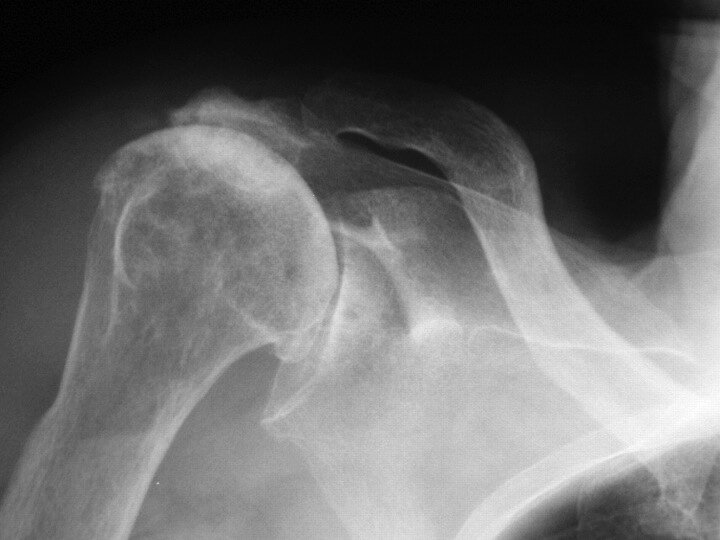

A 72-year-old woman is evaluated for chronic right shoulder pain associated with a large effusion.

A radiograph of the right shoulder is shown.

A. Basic calcium phosphate deposition

B. Calcium pyrophosphate deposition

C. Osteoarthritis

D. Rheumatoid arthritis

A. Basic calcium phosphate deposition disease (Milwaukee shoulder)